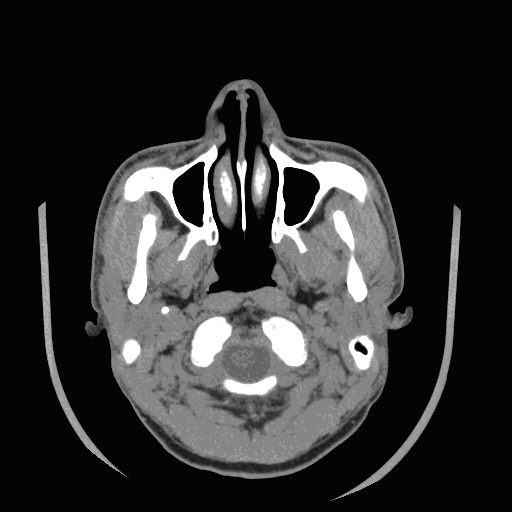

CT Image Sequence:

Based on the variable absorption of x-rays by different

tissues,

a

computed tomography(CT) imaging, also known as "CAT

scanning" (Computerized Axial Tomography)

is a diagnostic imaging procedure that uses a

combination of x-rays and computer technology to produce

a different form of imaging known as

cross-sectional images (often called slices), both

horizontally and vertically, of the body.

A CT scan shows detailed images of any part of the body,

including the bones, muscles, fat, and organs.

Spatial and contrast resolution are dependent on the

energy of the x-ray source, slice thickness, field of

view, and scanning matrix.

High resolution CT provides excellent delineation of

osseous structures. |

A CT

image created with an x-ray source is determined by the electron density

of the tissue.

Different

organs have different CT value in CT images. So, their colors will be

different too. In this head CT image, we can see that bones are white

while other parenchyma such as muscles and blood vessels are gray, even

dark.

Many

images slices like this can be combined to give a 3-D view of the head.

And this is what we are bending ourselves to. In the 3-D model of the

head, we shall see something the same as what we see in the

anatomization .